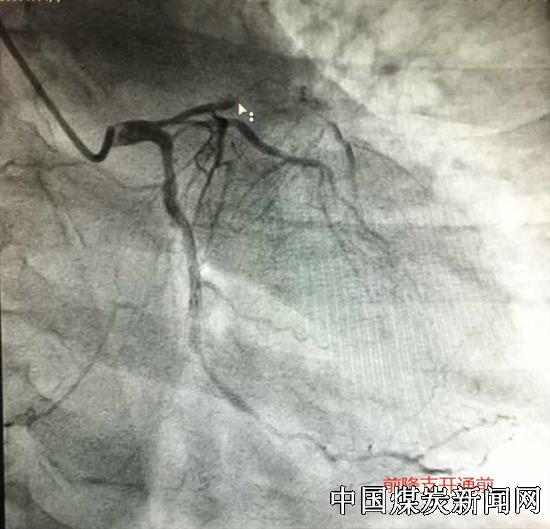

6月29日,51岁女性患者,因胸痛难忍来医院急诊。经诊断患者为陈旧性心肌梗塞(前降支慢性闭塞病变) 不稳定心绞痛(右冠开口病变)合并心功能不全,冠脉造影提示前降支近中段完全闭塞,远端可因侧支循环显影,右冠开口次全闭塞,回旋支远段亦完全闭塞,此为临床上所说的三支病变。这种病变首选的治疗手段是心脏搭桥手术,心脏搭桥手术又称冠状动脉旁路移植术通常在全身麻醉的情况下进行,需要开胸,手术时间长,创伤大,患者及家属考虑后不接受冠脉搭桥,要求尝试冠脉介入治疗。他们将希望及生命交给了心内科。心内科介入团队在赵军峰主任的指导下,尹威医师凭着丰富的手术经验及高超的专业素质,在与魏鹏辉医师的密切配合下,仅用两根导丝和娴熟的手法将前降血管打通并成功植入支架,使前降支再次重建,极大改善病人心功能,同时处理了右冠的开口次全闭塞病变,整个CTO手术过程仅用了两个多小时。此手术的技术难度在心脏介入治疗领域走在了当地先进行列!术后得到了患者及家属的高度认可及赞扬!